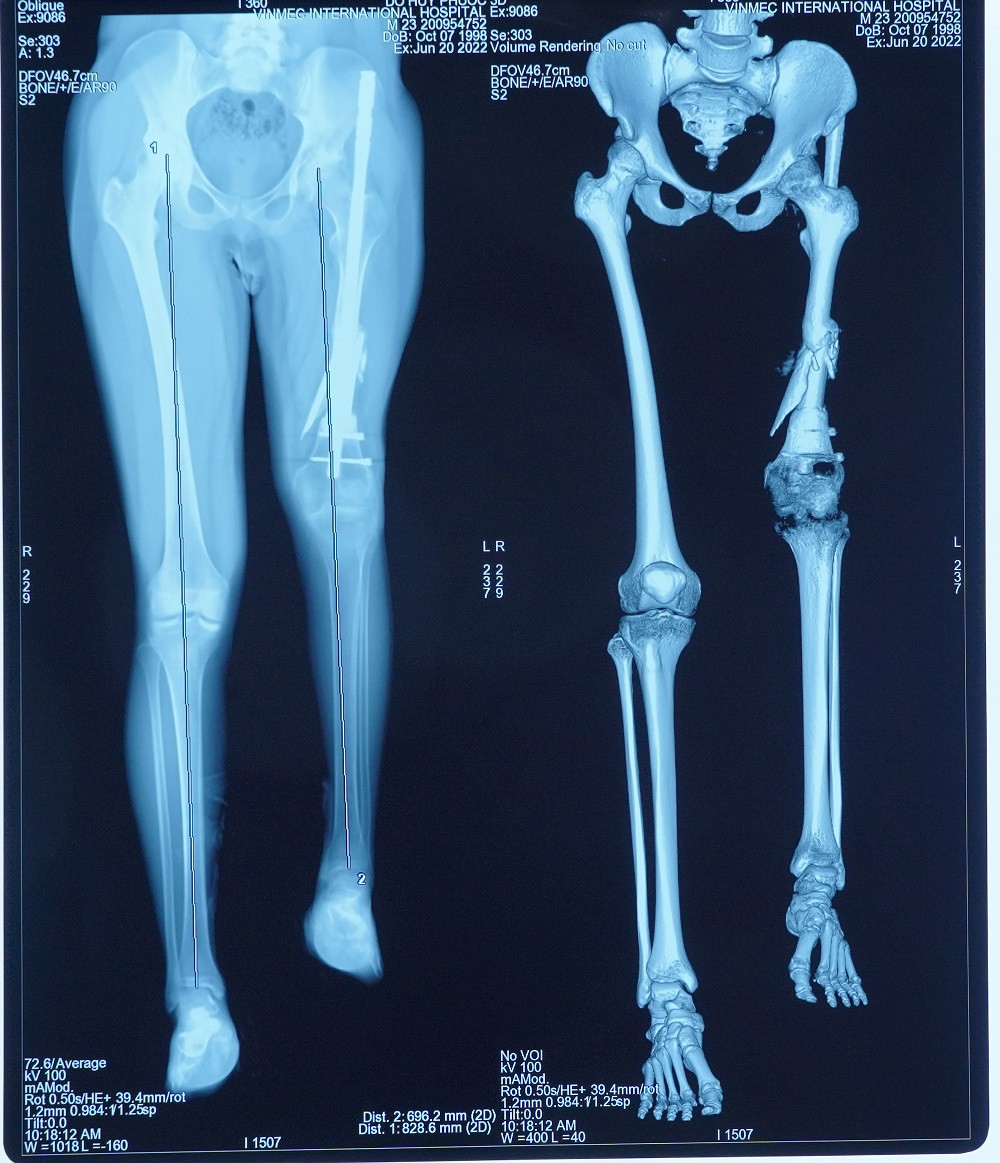

Sau khi chân trái được kéo dài tới 13cm, anh Đỗ Huy P. (24 tuổi, Đắk Lắk) đã có chiều dài 2 bên chân tương đương nhau. Về quê sau gần 3 tháng nằm điều trị ở Hà Nội, anh P. bỏ được một bên nạng, chỉ cần dùng nạng cho bên chân đã kéo, đồng thời rất tích cực tập phục hồi chức năng để cơ chân khỏe và nâng đỡ tốt. Theo tiên lượng của các bác sĩ, trong vòng 6 tháng anh có thể đi lại hoàn toàn bình thường.

Các bệnh nhân kéo dài chân thông thường (kéo cả 2 chân) sẽ được kết hợp kéo cả 2 xương trên và dưới đầu gối là xương đùi và xương chày. Trường hợp của anh P. nan giải hơn khi chỉ kéo dài một chân trái. Cái khó là làm sao để tránh tình trạng 2 đầu gối bên cao bên thấp. Chưa hết, vấn đề cần khắc phục chính là ở xương đùi ngắn và phần mềm tại đây co rút. Điều trị đúng nguyên nhân rất quan trọng và cũng là thách thức khi kéo dài một khoảng cách lớn ở riêng phần đùi.

Sau nhiều lần thăm khám, hội chẩn, GS. Dũng và ekip đã đi đến phác đồ điều trị 2 giai đoạn: Gỡ dính và kéo phần cơ đang co rút ra tối đa có thể, sau đó thực hiện phẫu thuật ghép xương đùi và đầu gối nhân tạo bằng vật liệu y sinh. Toàn bộ kích thước, trọng lượng xương nhân tạo sẽ được tính toán bằng công nghệ 3D để đảm bảo gần với chân lành nhất. Bệnh nhân đã 24 tuổi và ổn định chiều cao nên không lo bị chênh lệch chi và tránh nguy cơ gãy xương lần nữa, như vậy sẽ đi lại được bình thường.

| Phương pháp này đã thực sự mang lại cuộc sống mới cho bệnh nhân sau khi khắc phục được độ chênh lệch giữa 2 chân lên tới 13cm |